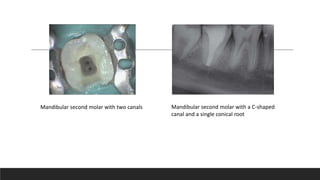

Mandibular second molar with two canals Mandibular second molar with a C-shaped

canal and a single conical root